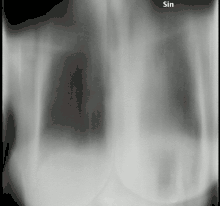

A fungus ball in the lungs may cause no symptoms and may be discovered only with a chest X-ray, or it may cause repeated coughing up of blood, chest pain, and occasionally severe, even fatal, bleeding.[2] A rapidly invasive Aspergillus infection in the lungs often causes cough, fever, chest pain, and difficulty breathing.

On chest X-ray and CT, pulmonary aspergillosis classically manifests as a halo sign, and later, an air crescent sign.[24] In hematologic patients with invasive aspergillosis, the galactomannan test can make the diagnosis in a noninvasive way. Galactomannan is a component of the fungal wall.[13] False-positive Aspergillus galactomannan tests have been found in patients on intravenous treatment with some antibiotics or fluids containing gluconate or citric acid such as some transfusion platelets, parenteral nutrition, or PlasmaLyte.[25][26]